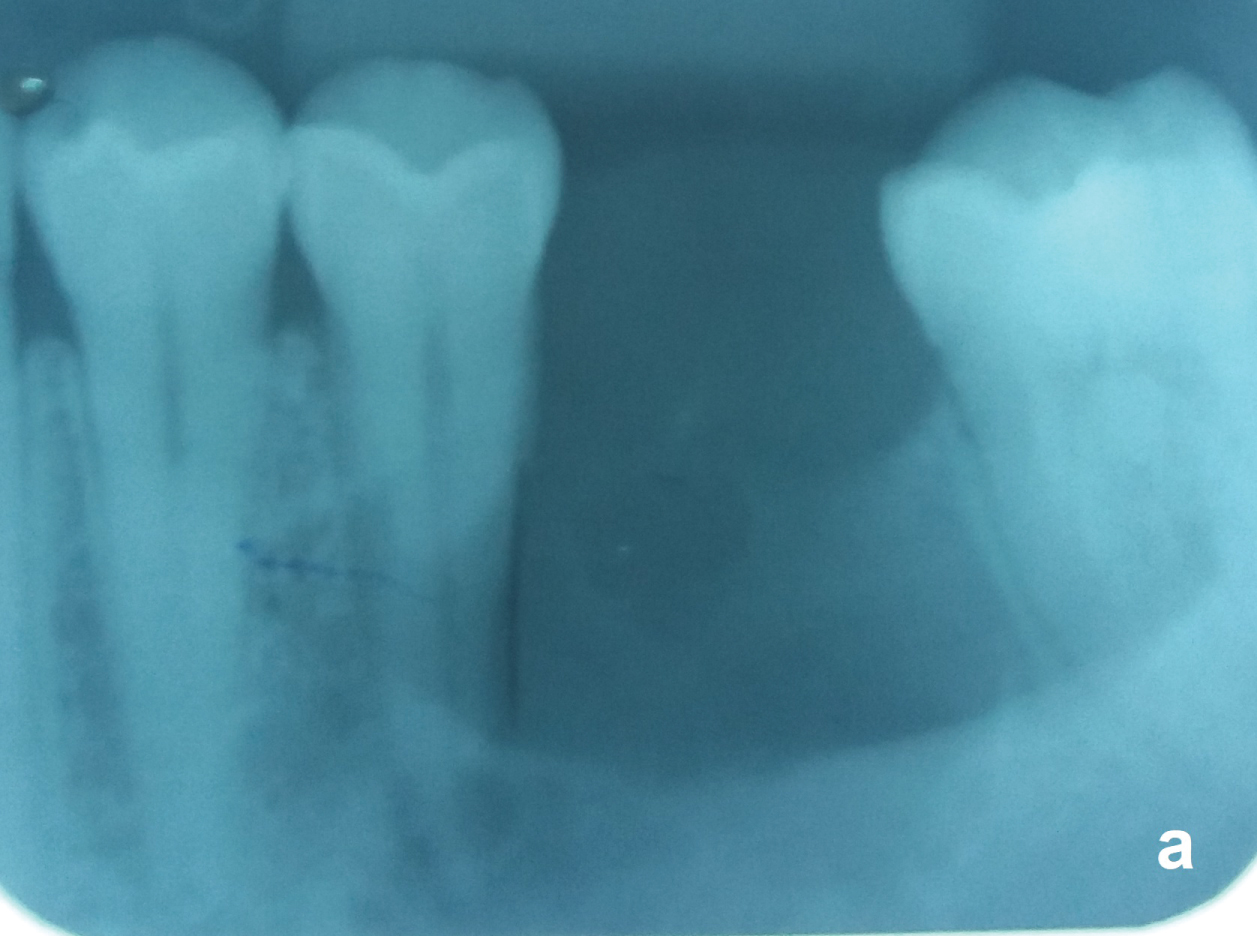

Nonvital teeth close to the OKC may be endodontically treated and maintained (Figure 5a and Figure 5b) but those with the cyst adhered on the radicular surface or with radicular resorption by the OKC should be removed. After total removal of the OKC, patients should receive a yearly radiological follow-up the first five years and beyond that every two years. Recurrences may occur over as long a period of 25 years [18].

Figure 5A: Same case of the figure 2. Unilocular OKC with a well-defined border between the nonvital tooth 35 and the vital tooth 37. Observe that the periodontal ligament of both teeth are preserved. View Figure 5A

Figure 5B: Tooth 35 was endodontically treated before the surgery. View Figure 5B